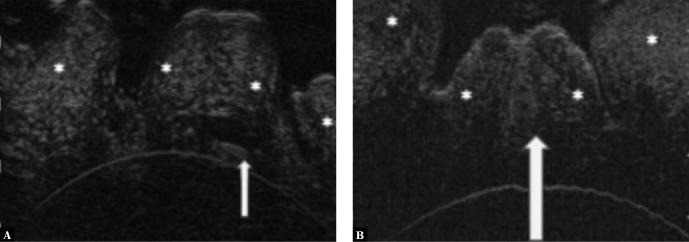

In this study, the individual layers of the skin in the area of the mons pubis, labia majora (together with hair follicles and sweat glands) and labia minora were successfully visualized in all the patients. The subepidermal low-echogenicity band was seen in the area of the mons pubic and labia majora in 40 cases. This concerned 100% of women who underwent cosmetic skin treatments. In all the patients, HFUS demonstrated the layered structure of the anterior and posterior vaginal walls, the walls of the urinary bladder and rectum, layers of the vaginal portion of the cervix and the external opening of the cervix.

在本研究中,所有患者均成功观察到阴阜、大阴唇(连同毛囊和汗腺)及小阴唇区域皮肤的各层结构。40例患者在阴阜和大阴唇区域可见表皮下低回声带。这涉及到所有接受过皮肤美容治疗的女性。在所有患者中,高频超声均显示了阴道前、后壁、膀胱壁和直肠壁、宫颈阴道部各层以及宫颈外口的分层结构。